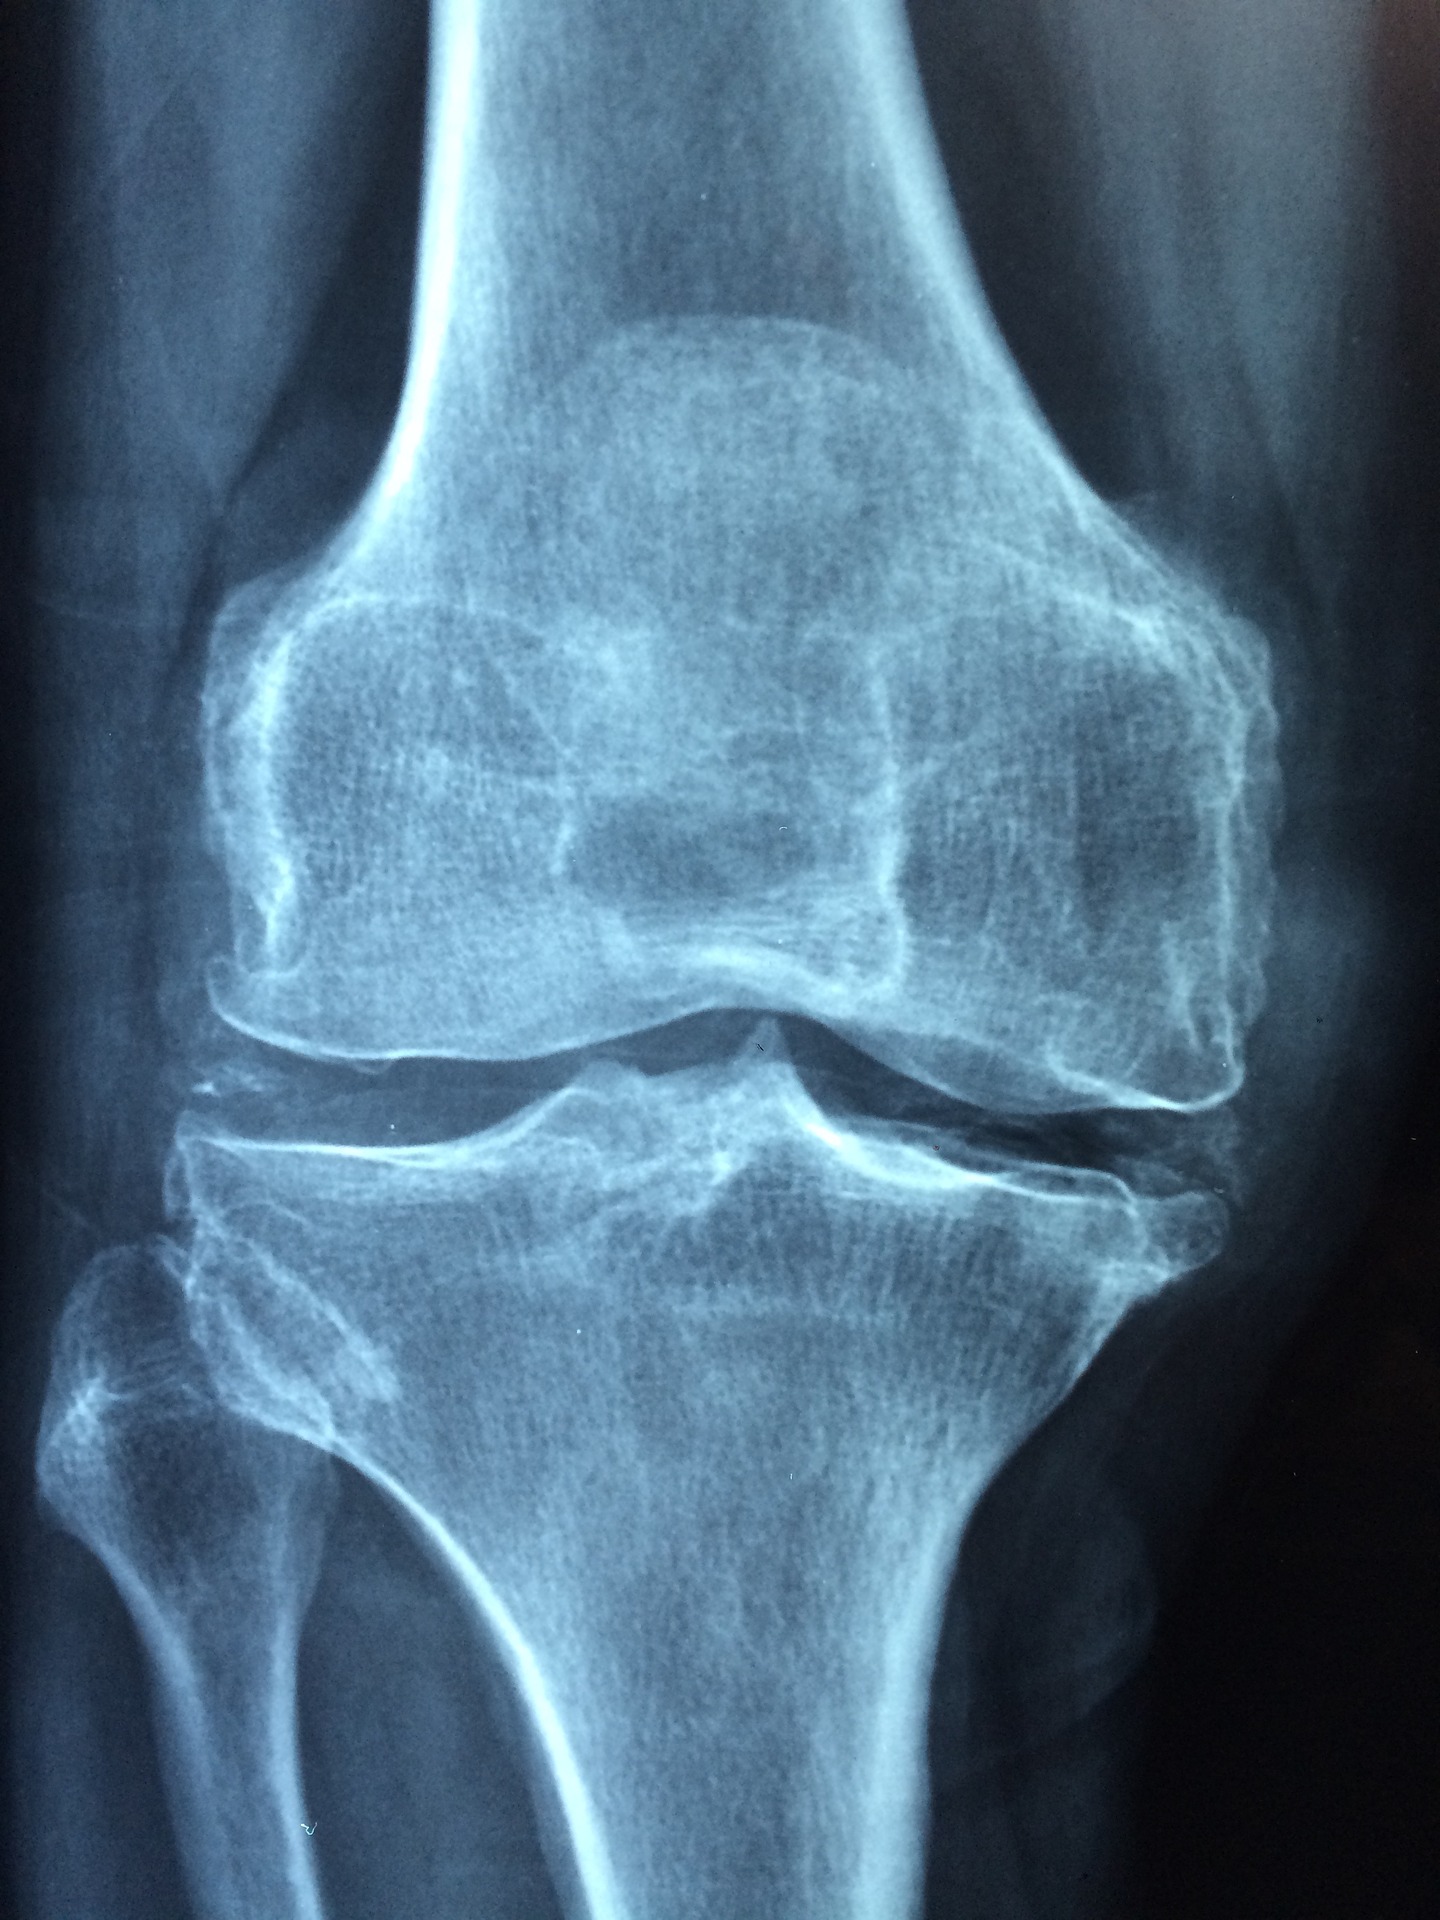

Diagnostyka jest przeprowadzona przez lekarza, który zleca zazwyczaj badanie kliniczne, radiologiczne oraz histologiczne. Poprzez zdjęcie rentgenowskie, można zaobserwować zmiany w obrębie kości, poprzez widoczne szarobiałe ogniska chrzęstne. Mogą mieć charakter zlewających się ze sobą lub podzielonych. Lekarz również, poprzez badania zdiagnozuję transformacje złośliwe guzów o charakterze nowotworowym. Choroba Olliera nie wykazuję objawów, jednak istnieje możliwość uciskania rozdymanych tkanek na nerwy.